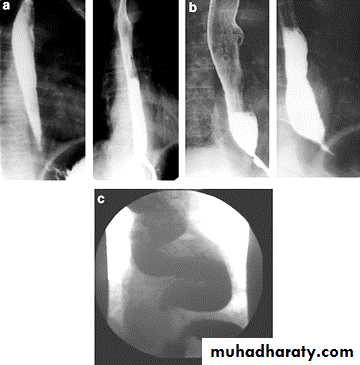

Narrowing :

the narrowing is Constant Short length (confined to cardia).

Regular and smooth.

No shouldering sign.

Tapering (Tip of pencil , cigar shape) Under left dome of diaphragm.

DILATATION (Sac like in proximal part )

Undulating or spiky out line due to sluggish peristalsis.

Non- homogeneity of Barium due to food particles.

Air Barium level.

CXR shows widening of mediastinum.

Absence of fundal gas shadow.

Basal fibrosis in lungs due to repeated aspiration pneumonia .

LEFT: Dilated esophagus (arrows) appears as long, well-defined structure paralleling heart RIGHT: Dilated esophagus usually deviates to right. Narrowing (arrow) at hiatus.

LEFT: CT shows dilated esophagus (arrow) that led to esophagram.RIGHT: Esophagram shows narrowing (arrow) at level of hiatus.